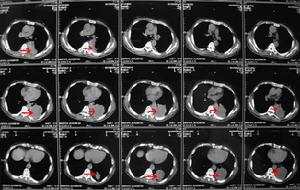

1.影像學檢查 為了在治療前準確定出臨床分期以利於客觀地制訂治療方案可行髂動脈旁腹主動脈旁淋巴的B超CT、磁共振和淋巴造影等檢查。